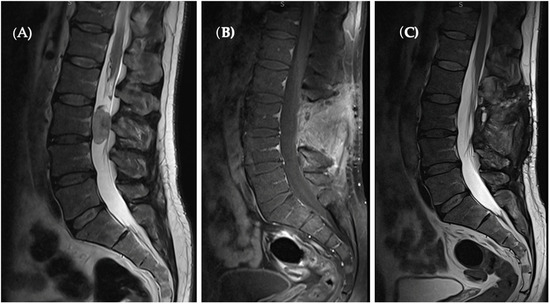

Subsequent MRI imaging undertaken after a one-year period displayed no evidence of tumor recurrence, precluding the necessity for adjuvant therapy (Figure 3).

Figure 3.

(A) Pre-op T2 sagittal MRI revealed a hyperintense oval-shaped lesion located at the L3 level occupying spinal canal. (B) Sagittal T1 with contrast enhanced as well as T2 sagittal. (C) Sections present a complete tumor removal and no sign of recurrence.